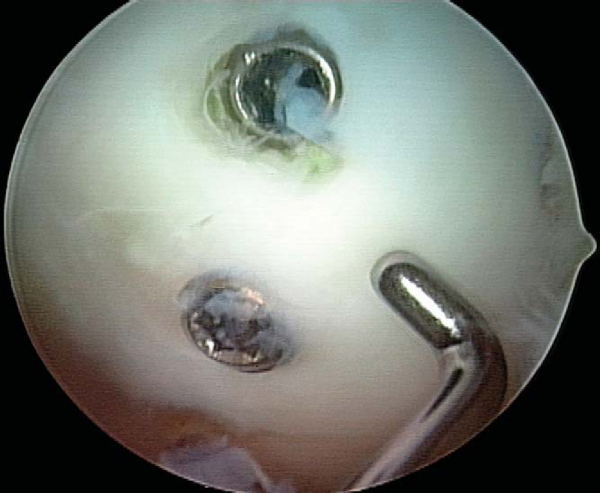

With use of an ipsilateral viewing portal, a guide wire is introduced through the accessory instrumentation portal and drilled into the lesion (

Fig. 53-9

). A second guide wire is then placed to provide countertorque during drilling and placement of the first screw (

Fig. 53-10

). Small lesions may permit use of a single screw for adequate fixation, but larger lesions may require two or even three screws, and careful consideration should be given to the spacing of implants to avoid crowding and fracture of the osteochondral flap. As these lesions occur in a younger population with excellent bone quality, implants will typically obtain tremendous purchase and can easily generate excessive compression at the lesion site, fracturing the osteochondral flap if overtightening is allowed (

Fig. 53-11

). Slight overdrilling is necessary at times to avoid overtightening. When cannulated implants are used, it is helpful to remove the guide wire once the screw has been seated two thirds of the way and to finish seating the screw with a noncannulated screwdriver. This avoids difficulty in removing the guide wire and eliminates the fracture risk to a cannulated screwdriver tip by the torque generated by the compression screw. Implants are countersunk to permit range of motion without risk of injury to the opposing articular surface. After fixation, the lesion is probed for stability and observed through several cycles of flexion-extension for flap motion (

Fig. 53-12

).